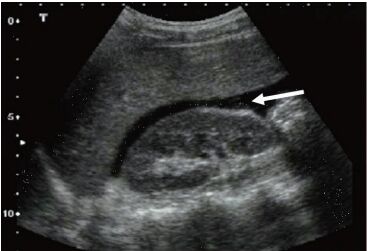

39. 75 歲女士主訴呼吸喘、呼吸困難、頭暈且全身無力、同時合併胸痛不適,血壓 78/49mmHg,心跳約 40 次/分鐘,心電圖監視器顯示如下圖,下列敘述何者為是?

(A)此為第一度房室傳導阻斷(1

o AV Block),不需要緊急治療心律,可以先觀察症狀。 (B)此為第二度房室傳導阻斷(2

o AV Block) Mobitz 第一型,不需要緊急治療心律,可以先觀察症狀。 (C)此為第二度房室傳導阻斷(2

o AV Block) Mobitz 第二型,先給予 Atropine 1mg 靜脈推注。 (D)此為第三度房室傳導阻斷(3

o AV Block),因病人症狀不穩定,可考慮使用 TCP。